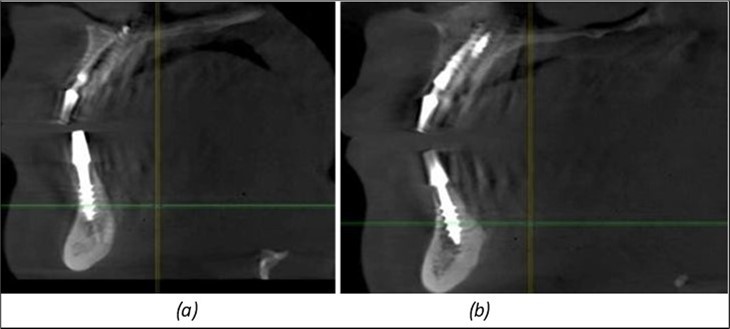

Figure 13.Corticobasal BCS implants fixed between the vestibular and lingual cortices with support on the basal bone: (a) BCS fixed between the lateral cortices; (b) BCS implant with support on the basal cortex.

Figure 14.Rx panoramic final situation control: (a) Panoramic X-ray with the addition of a distal BCS implant in quadrant 3 at 11.2022; (b) Control X-ray, 10.2023.